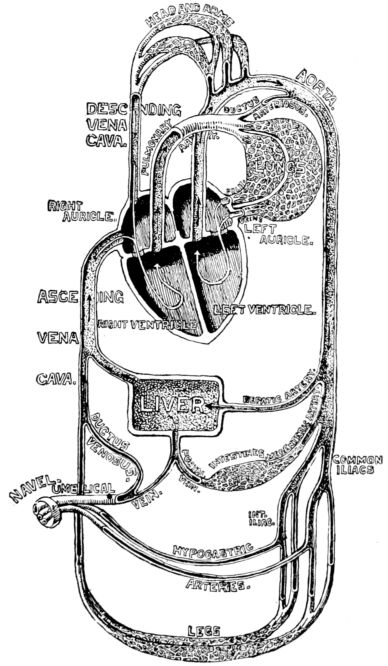

| xx28. | Diagram of fetal circulation | 85 |

| 29. | Diagram of circulation after birth | 87 |